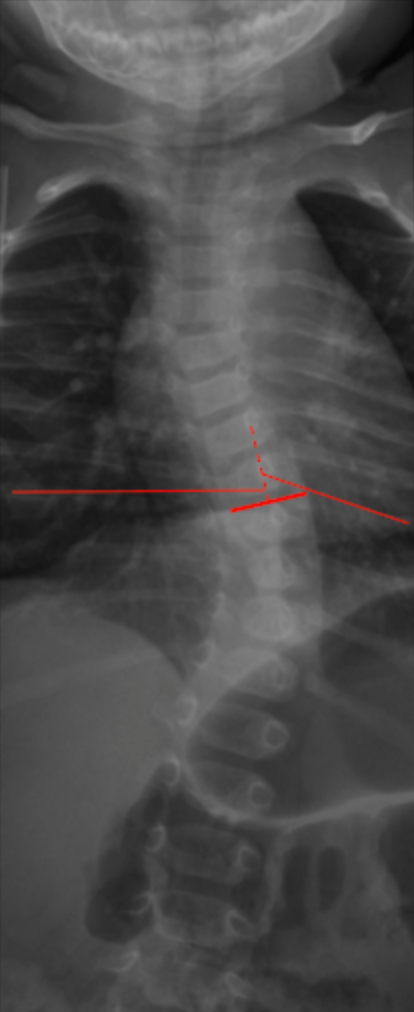

Rib–Vertebra Angle Difference (RVAD) is a coronal plane radiographic measurement used to assess curve progression risk in infantile idiopathic scoliosis. It quantifies the asymmetry of rib orientation relative to the apical vertebra on the convex and concave sides of the curve.

• Identify the apical vertebra of the primary scoliotic curve.

• At the apical level, identify the most medial aspect of the ribs on both the convex and concave sides.

• On each side:

• Draw a line along the long axis of the rib adjacent to the apical vertebra.

• Draw a second line along the superior endplate of the apical vertebra (or a horizontal reference line).

• Measure the rib–vertebra angle on both the convex side (A) and the concave side (B).

• Calculate the Rib–Vertebra Angle Difference (RVAD):

RVAD = A - B